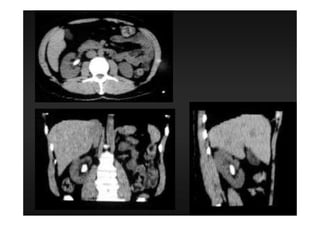

TOMOGRAFIA

COMPUTADORIZADA

Definição

É um método diagnóstico, no qual

são utilizados feixes colimadores,

muito finos, de Raios X, acoplados a

computadores que favoreçam

imagens detalhadas de seguimentos

corporais.

TC axial

TC helicoidal ou espiral

AXIAL

• Imagens em um plano transversal ao objeto a

partir de um giro de 360 graus do feixe de raio

X em torno de si (mesa estática).

HELICOIDAL OU ESPIRAL

• Rotação contínua da ampola de raio X

acoplada em movimento continuo e regular em

torno do paciente em cima da mesa (aquisição

volumétrica) cortes de 1,0 a 10,0 mm de

espessura.

Reconstrução em planos diversos do

transversal são também mais fidedignos.